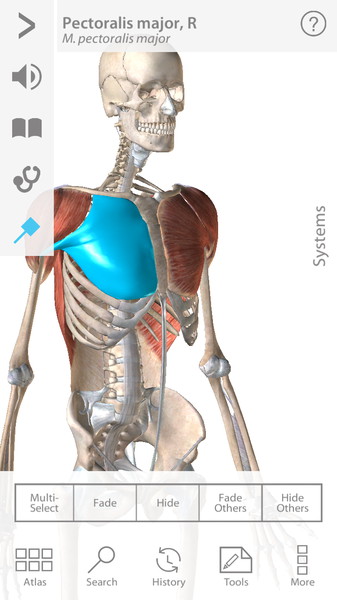

Human Anatomy Atlas 7.4.03

Полностью интерактивный 3D анатомический атлас для Android станет настоящей находкой для всех пользователей, так или иначе связанных с медициной. Врачи и профессора всего мира используют Visible Body 3D Anatomy Atlas, чтобы интерактивно и визуально изучать человеческое тело.

Трехмерный атлас по анатомии рассматривает модели мужской и женской анатомии. Для этого достаточно будет выбрать F или M. Далее воспользуйтесь удобным поиском по системам (Select System) и Вы сможете рассмотреть любое сочетание анатомических образований на черном или белом фоне, прочитать и услышать их полное описание (положение, форму, функциональные и физиологические особенности). Приложение само по себе очень чувствительно. Удивительно то, что при максимальном увеличении изображение не теряет своей детализации. Пользователь в полной мере сможет воспользоваться жестами многозадачности и понимание строения человека будет максимально эффективным.

- Каждая модель содержит порядка 4600 анатомических образований.

- Модель можно вращать, наклонять, приближать – одним словом, изучать под любым углом.